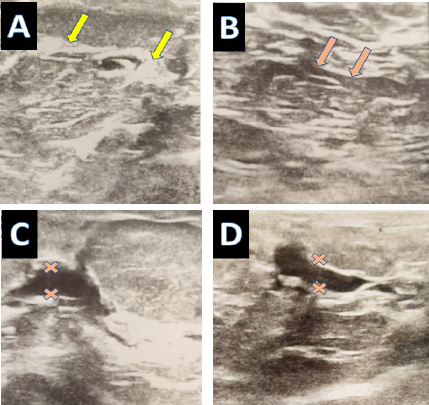

Typical fibrocystic changes in breast tissue are (A) Abundant fibrous tissue bands and (B) prominent thin wall ducts. Localized prominent ductal changes; (C) Thickened walls, dilated, irregular ectatic ducts that have internal echo-free contents suggesting intraductal proliferation and periductal inflammation; and (D) dilated ducts with adjacent microcytic changes.